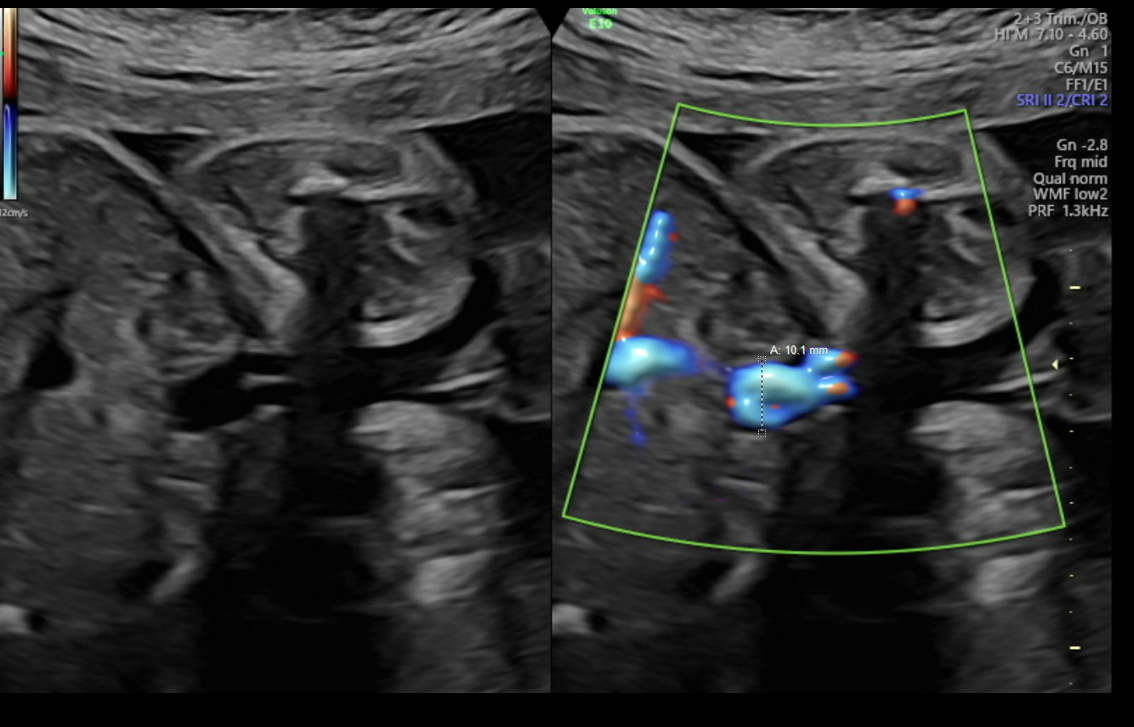

Diagnostic criteria for UVV and the WFUP protocol for subsequent evaluation and surveillance is described in (Table 1) and was followed for all maternal-fetal pairs. UVV characteristics documented during each ultrasound included: size, directionality of blood flow (unidirectional or bidirectional), presence of turbulence, and presence of a filling defect; see (Figures 1a-1c).

Figure 1a. Unidirectional or nonturbulent flow without filling defect.

Figure 1b. Bidirectional or Turbulent flow without filling defect.

Figure 1c. Bidirectional flow with suspected filling defect.

Filling defects were recorded when sonolucent absence of color flow was demonstrated with color Doppler within the UVV. Filling defects were interrogated in transverse and sagittal abdominal views along with color Doppler sweeps to confirm the filling defect and overcome the artifact loss of signal with flow perpendicular to insonation. The presence of UVV and its characteristics was confirmed on repeat ultrasound within 7 days while having monitoring in the interim for fetal well-being. All recorded fetal sonographic measures were uniformly collected by WFUP’s American Institute of Ultrasound in Medicine (AIUM) accredited ultrasound unit by a Registered Diagnostic Medical Sonographer. Voluson E10 General Electric ultrasound machines, with abdominal probe 4-8 and 4 mHz frequency, were used. All WFUP patients are offered genetic counseling and genetic screening as appropriate, including this study’s participants.